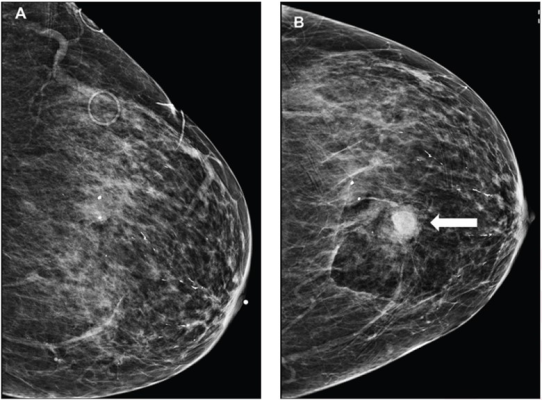

85-year-old patient who maintained daily use of 81 mg of aspirin at time of stereotactic-guided core-needle biopsy of group of breast calcifications; pathologic assessment yielded atypical ductal hyperplasia. Left craniocaudal (CC) mammographic view obtained before (A) and after (B) biopsy show hematoma on postbiopsy image (arrow), measuring 1.2 cm.